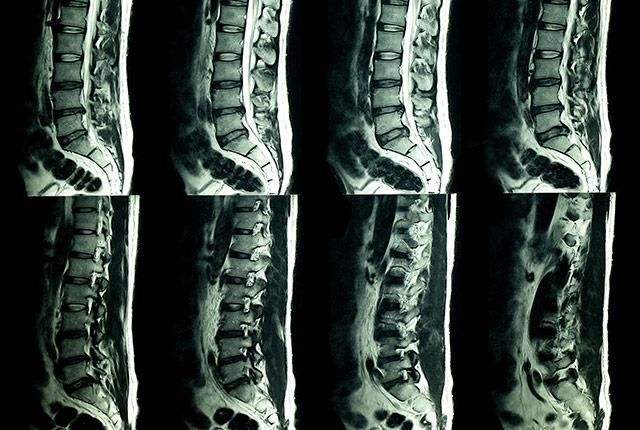

Your spine deteriorates naturally over time, even if you tread lightly and are mindful of good posture. Radiologists are keenly aware of this truth due to an endless queue of patients with low back pain whose imaging scans reveal no acute injury but, instead, show typical signs of activity, gravity, and aging.

UW Medicine researchers explored what would happen if patients’ imaging reports—terse anatomic observations of “disk height loss” and other findings—also included plain-language context that such findings are commonly seen in people who have no pain.

“We thought this extra information would reassure the clinician and the patient that the finding is in the range of ‘normal’ for their age group, and lead to conservative treatment,” said the study’s lead author, Dr. Jeffrey Jarvik, a professor of radiology at the University of Washington School of Medicine.